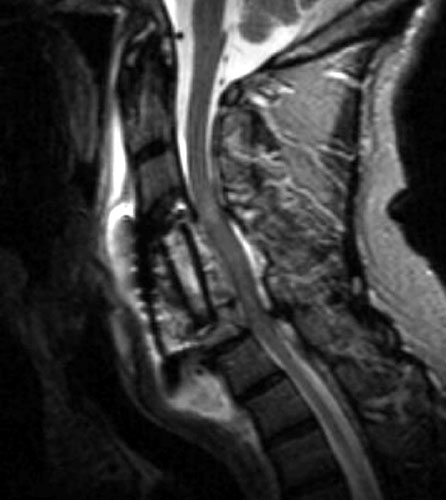

A B C Sagittal T2 FSE (A), sagittal T1 pre (B) and post contrast administration (C) show the graft with blooming artifact where the plate exists anteriorly as well as the screw (lower portion of the image). The susceptibility artifact of the screw shows its ventral positioning essentially outside of the C7 vertebral body. Also, there is T2 hyperintense fluid surrounding the surgical site with the graft material is now surrounded by nonenhancing mixed signal intensity material, predominately hypointense on T1 and hyperintense on T2, possibly suggesting some blood products. There is enhancement in both the anterior and posterior epidural spaces. The distal end of the fixation plate with the screw in the C6 vertebral body appears now displaced anteriorly and there is significant prevertebral soft tissue swelling. Also, this fluid- like material surrounding the bone graft appears to cause some narrowing of the spinal canal, with some mild spinal canal stenosis.